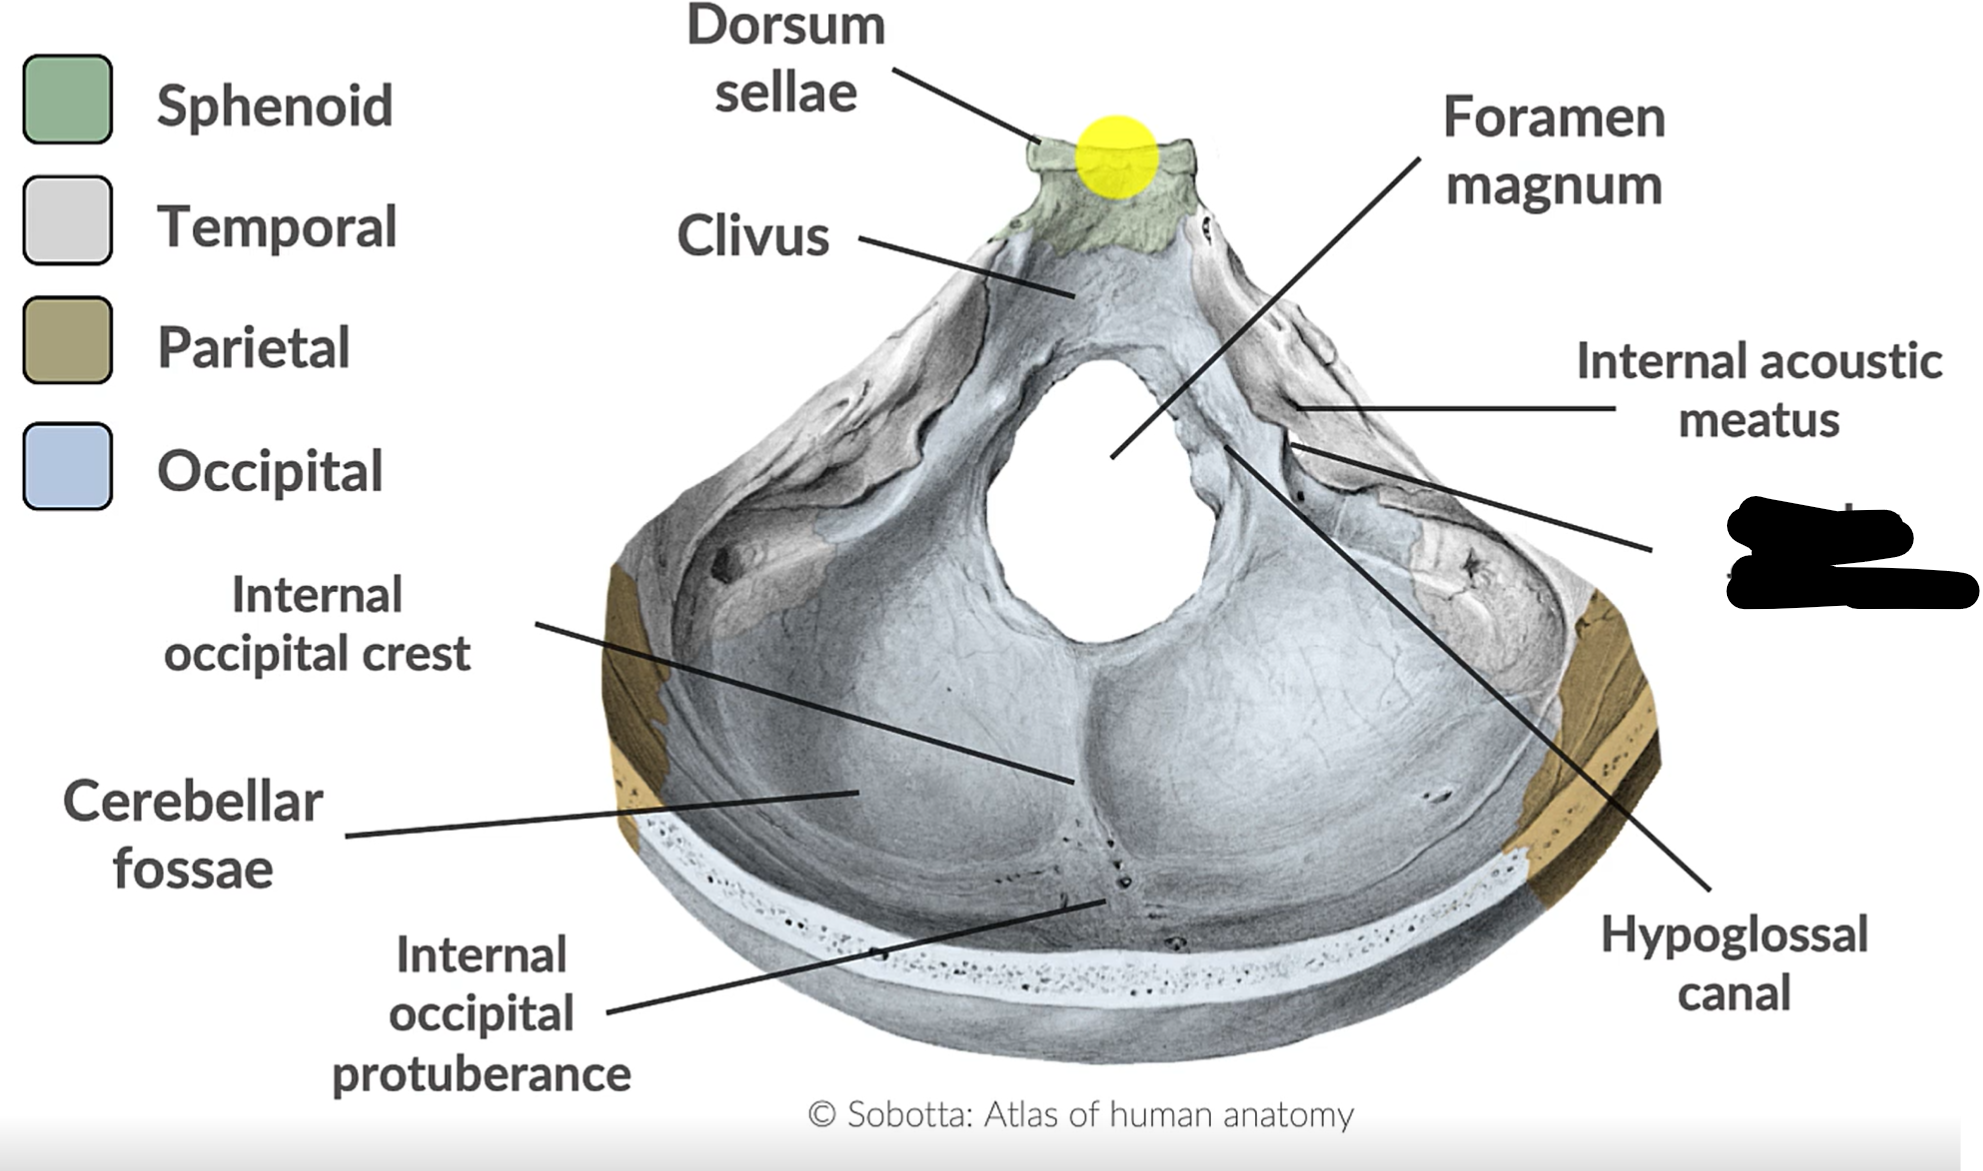

What forms the posterior cranial fossa?

Occipital, temporal, parietal and sphenoid bones

Foramen magnum

Jugular foramen

Internal acoustic mediatus

Hypoglossal canal